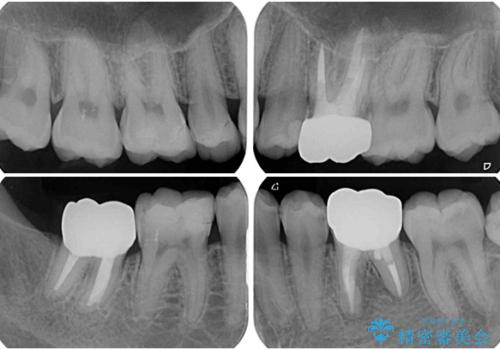

- 治療中の前歯と口腔内にある銀歯が気になるとのことで来院された患者様です。

土台に含まれている金属も含め、口腔内の金属は全て除去し、根管治療が必要な歯は根管治療を行い、オールセラミッククラウンやセラミックインレーにて治療することとしました。

途中来院されない時期があったため、初診から終了まで期間がかかりましたが、根管治療を行った歯の根尖病変はいずれも改善を確認することができました。